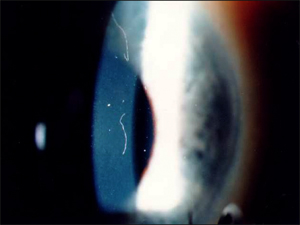

Img1

スライド#1 角膜接合部分の繊維